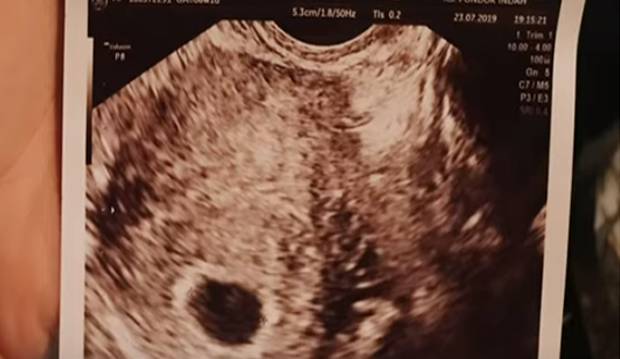

Yuanita menceritakan pada tanggal 21 Juli lalu, dirinya melakukan tes kehamilan. Mencoba dua alat tes kehamilan, Yuanita kaget mengetahui hasilnya positif. Kini kehamilan Yuanita Telah memasuki bulan ketiga.

“21 Juli aku cek melalui alat tes kehamilan, ada dua macam yang cek digital serta cek manual. Waktu cek manual, hasil dua garis tapi satu garisnya samar-samar, aku bangunin suami yang lagi tidur bilang bahwa aku positif. Lalu aku cek pakai alat cek digital, hasilnya keluar yes, ialah positif hasilnya. Gue langsung happy serta pelukan sama suami,” kisah Yuanita tentang mengetahui kehamilan pertama kali.